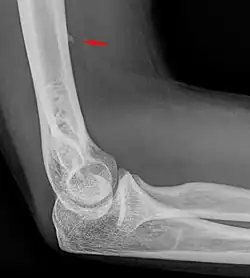

Der Processus supracondylaris ist eine seltene atavistische Bildung an der vorderen ulnaren Seite des distalen Endes des Oberarmknochens (Humerus), etwa 6 bis 7 cm proximal des Gelenkspaltes. Synonyme sind Processus supracondylicus, Tuberculum supratrochleare, Humerussporn und englisch Humeral supracondylar spur. Es handelt sich um einen knöchernen Fortsatz, der bei 0,7 % – 2 % aller Menschen vorkommt.[1] Die Erstbeschreibung geht auf den Anatomen F. Tiedemann im Jahre 1822 zurück.[2] (zitiert nach[3])

Die Arteria brachialis und der Nervus medianus verlaufen bei vorhandenem Processus supracondylaris durch einen osteofibrösen Kanal, den Canalis supracondylicus, der zur Kompression der beiden Strukturen führen kann.[4]